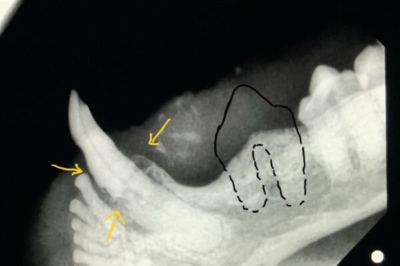

下顎のレントゲン写真

黄色矢印は歯周病(歯槽骨の拡大 )と吸収病巣で黒い隙間ができている犬歯の病変。口内炎でなくても抜歯対象。黒い囲みは吸収病巣で失われた歯があった部位。この部位の骨と一体化した歯根は可能な限り削る。